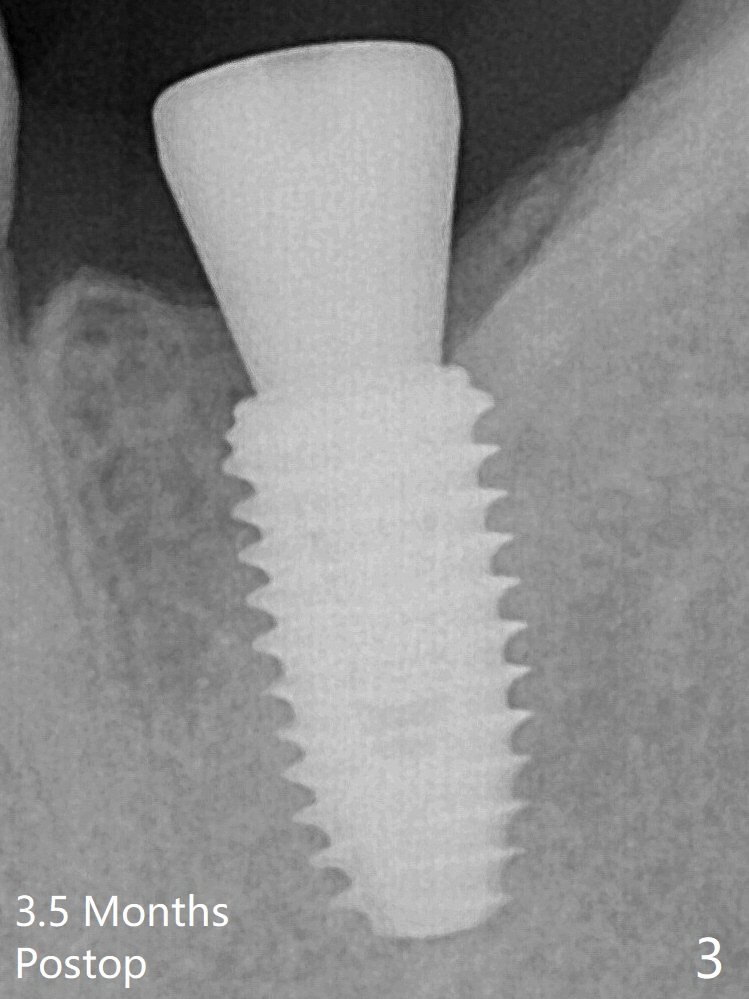

A 5x10 mm implant is placed with guided surgery in ~10 minutes. When a 5.5x5 mm healing abutment is placed, hemostasis is achieved (Fig.1). There is no bone loss around the implant 3.5 months postop, which suggests that it is an atraumatic procedure (Fig.3).